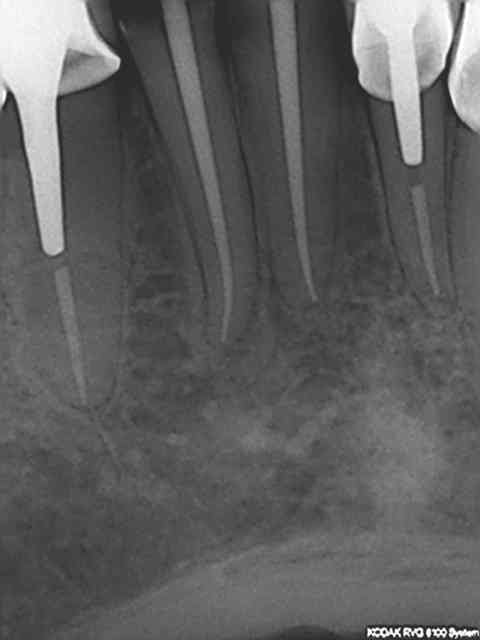

Regardez les endo de chicot29, mono cone et postez vos endo thermo et on compare !

Je fais du mono cone et je n'ai pas honte de mes endo.

Et effectivement un cone en 6 % n'a rien à voir avec un cone en 2%. L'efficacité tu la vois avec le temps, et un bon mono-cone scellé à l'apex donne des résultats plus que corrects. Je thermo-compacte au machtou quand je fais l'empreinte dans la séance de l'endo)))))